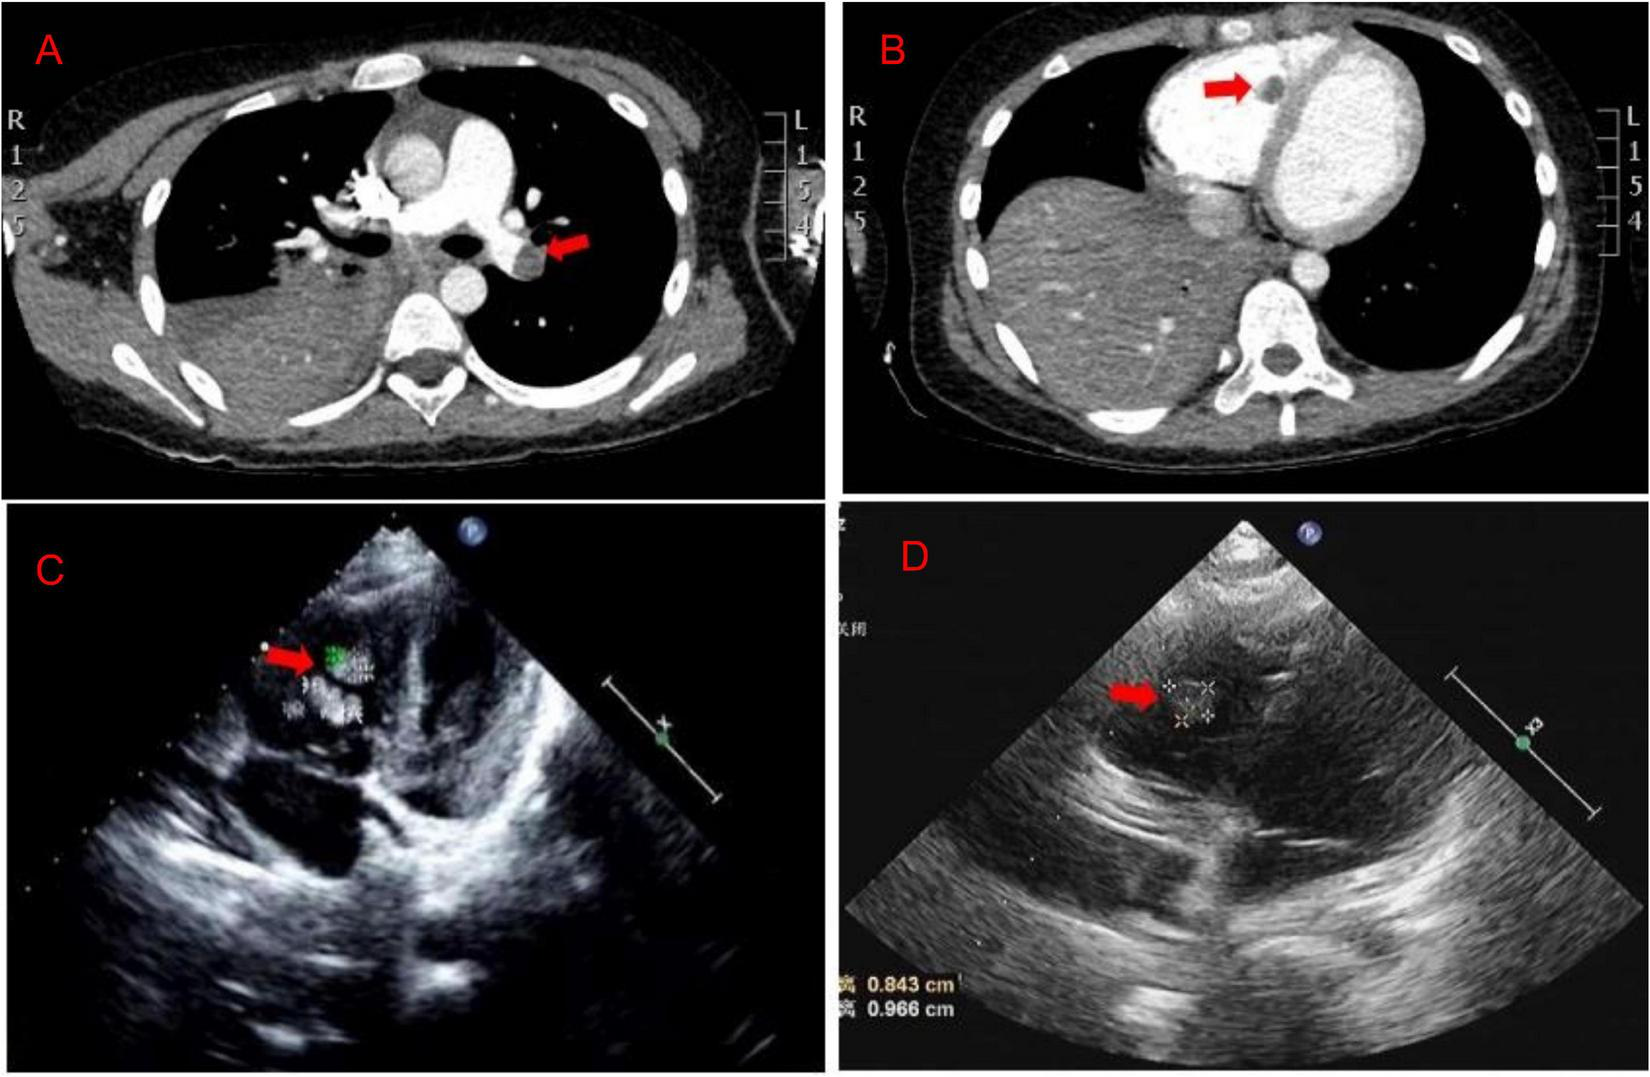

A previously healthy 8-year-old girl was referred to the Department of Respiratory at Tianjin Children’s Hospital (China) for 5 days of high fever and 2 days of violent coughing. The patient had no related histories of congenital metabolic disease, congenital heart disease, cardiovascular surgery, family thrombus, antiphospholipid antibody syndrome, systemic lupus erythematosus, dilated cardiomyopathy, nephrotic syndrome, inflammatory bowel disease, etc. During the course of the disease, there was no hemoptysis, fatigue, and syncope in the patient. A lung computed tomographic (CT) scan revealed a massive consolidation shadow in the right lung lower lobe and pleural effusion. Despite intravenous administration of ceftriaxone (80 mg/kg/day) and azithromycin (10 mg/kg/day) for 3 days at the local hospital, fever and respiratory status continued to deteriorate. Therefore, she was referred to our hospital on 30 July 2019. Evaluation of her cold agglutinin titer of MP-IgM revealed 1:160 while C-reactive protein level was >200 mg/L. She was administered intravenous latamoxef (80 mg/kg/day) combined with azithromycin (10 mg/kg/day) as anti-infection medications and methylprednisolone (2 mg/kg/day) as an anti-inflammatory medication. On day 2, elevated inflammatory marker and liver function levels were detected (neutrophil ratio 90%, ferritin 653 ng/L, lactic dehydrogenase 653 U/L, alanine aminotransferase 109 U/L, and aspartate aminotransferase 29 U/L). MP-DNA concentration in bronchoalveolar lavage fluid was 5.0 × 107 copies/ml. There were no bacteria, fungus, or viruses (adenovirus, respiratory syncytial virus, influenza virus, rhinovirus, human metapneumovirus, Rhinovirus, and Epstein Barr virus) found in sputum, bronchoalveolar lavage, and blood. On the third day, she developed a sudden pain on the right side of her neck and dyspnea. Echocardiography (Figure 1C) revealed multiple mass echos in the right ventricle (4 × 3 mm, 13 × 5 mm, and 9 × 5 mm). There was no enlargement of the right ventricle and right atrium. Echocardiography showed ejection fraction was 77%, left ventricular short axis shortening was 45%, with normal ventricular wall motion and systolic function. The children had normal blood pressure, without enlargement of the liver and enlarged jugular vein. There was no galloping rhythm in heart auscultation. The myocardial enzymes and myocardial injury markers in the patient were also normal. Chest CT angiography showed a filling defect in the left lower pulmonary artery and right ventricle (Figures 1A,B). Coagulation analysis revealed elevated D-dimer levels (10 mg/L; normal reference range, 0–0.55 mg/L) and fibrinogen (FIB) (6.683 g/L; normal reference values, 2–4 g/L). Based on these findings, cardiac multiple thrombus and pulmonary thromboembolism was suspected (Table 1). This disease is life-threatening and usually treated by surgical intervention for fear of thrombus detachment and caused new thromboembolism. However, the patients’ parents opted for conservative medical treatment. Therefore, she was administered with intravenous urokinase (initial 4,400 IU/kg, 10 min, later 4,400 IU/kg/h, q12h, total 5 days) for thrombolysis, low molecular weight heparin calcium (200 IU/kg/d, q12h) for anticoagulation and aspirin (4 mg/kg/day) to inhibit platelet aggregation. The symptoms improved after thrombolysis for 9 h, and only two massive echoes (9 × 5 mm and 13 × 5 mm) were found in the echocardiogram after 11 h. We also explored the thrombophilia screen. Plasma protein C activity 152.3% (normal reference values, 70–140%), plasma protein S activity 46.85% (normal reference values, 70–123%), Antithrombin III activity increased by 132.2% (normal reference values, 75–125%). Anti-nuclear antibodies (ANAs) were positive, titer 1:100, karyotype: Golgi and granular type. Anticardiolipin (aCL) antibodies and anti-β 2-glycoprotein antibodies were both negative, while lupus anticoagulant (LA) was positive. There was no definite pathogenic mutation in the screening of thrombotic disease-related single gene genetic diseases.

(A,B) The chest CT angiography showed a filling defect in the left lower pulmonary artery and right ventricle. (C) Echocardiography revealed multiple mass echos in the right ventricle (4 × 3 mm, 13 × 5 mm, and 9 × 5 mm) on day 3. (D) Echocardiography revealed mass echos in the right ventricle (8 × 13 mm) on day 12.

After 10 days of hospitalization, her condition gradually stabilized and the filling defect of the left lower pulmonary artery was decreased by CTA in the lung. Administration of low molecular weight heparin calcium was changed to rivaroxaban (15 mg/qd) as the anticoagulation therapy. However, on day 12, the patient suddenly complained of pain in the right shoulder and intercostal region and fidgety. Echocardiography (Figure 1D) showed a right ventricular mass echo (8 mm × 13 mm). One of the right ventricular thrombus had disintegrated and caused a new pulmonary embolism. She was treated with urokinase (4,400 IU/kg/h, q12) for 3 days again (Figure 2), and rivaroxaban anticoagulation therapy was continued. On day 13, she did not complain of pain in the shoulder or intercostal region. Hospitalization was continued for 30 days and the echocardiography still showed a mass echo (about 6 mm × 11 mm) in the right ventricle. After which she was discharged and oral rivaroxaban administration was continued. After 2 and 3 months of follow-up, there was no cardiac thrombosis and pulmonary embolism respectively. In 2 years of follow-up, we found no recurrence of thrombosis in the heart and lungs.